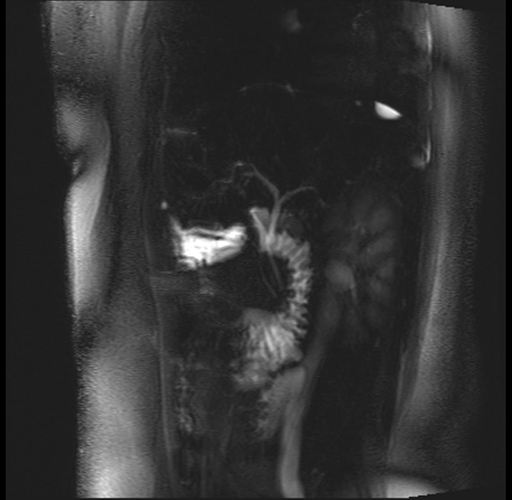

Imaging Analysis

Look through the patient's CT scan to identify any areas of concern for the necessary procedure.

Based on your CT findings, which issue(s) are present and would give reason for "planned slowing down moment(s)" in this case?